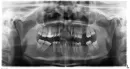

Год назад мне установили имплант на верхнюю шестерку, зуб отсутствовал около года. Это была, моя вторая имплантация в данной клинике, первый имплант устанавливали на нижнюю шестерку 2 года назад, все прошло успешно. После установки импланта дома в зеркале я увидела, что сквозь швы виднеется заглушка. Обратилась к хирургу, она сказала, что это нормально. К моменту снятия швов заглушка была видна полностью. Мне сказали, что все хорошо и отправили на полгода на приживление имплант.

Спустя полгода мне установили формирователь и направили на консультацию к ортопеду. Ортопед, сказал, что установка коронки не является возможной, что не хватает ткани, и коронка будет оголена. Хирург после этого решила подсадить мне костную ткань (какие-то искусственные материалы, не моя ткань). Операцию провели, хирург отпустила меня на пару месяцев и когда ткань прижилась, я снова пришла к ортопеду. Он опять мне сказал, что коронку установить невозможно, что необходимо вынуть этот имплант и установить новый. В день операции хирург изо всех сил, пыталась выкрутить имплант каким-то специальным инструментом, что-то сверлила, крутила, но так и не смогла достать его. Сказала, что он сильно прирос к кости и, что не вышло, его достать, сделала какие-то насечки на кости и опять подсадила костную ткань. Сказала, что можно было его выпилить, но это слишком опасная процедура и она на нее не пошла. На последующей консультации хирург сказала, что десна достаточно объемная, что очень довольна полученным результатом и отправила на приживление еще на пару месяцев. Пришла я опять спустя это время к ортопеду, он снял слепки и сказал, что часть импланта оголяется и если установить коронку, то он будет виден и будет туда забиваться пища и что такая коронка не простоит и года, что необходима опять операция, четвертая по счету уже на этот имплант, что раз его не получилось выкрутить, то другой уже хирург, который является, главным врачом в их клинике будет мне выпиливать его и устанавливать временную коронку непосредственно в день имплантации. Не уверена, что решусь еще на одну операцию, так как морально и физически уже истощена, ведь после каждой операции приходиться еще принимать антибиотики и другие лекарства, а так же терпеть боль.

- Опасно ли оставлять имплант с формирователем, не вынимать и поставить мостовидный протез (ортопед сказал, что имплант инфицирован)? Не возникнет ли воспалительного процесса под протезом из-за того, что остался имплант?